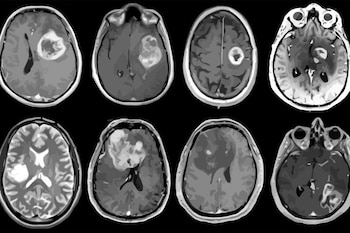

5. El biomarcador genético que detecta tumores cerebrales agresivos

Por otro lado, la investigación sobre tumores cerebrales reveló que la alta expresión del gen TERT en meningiomas, el tipo más común de tumor cerebral, se asocia a una progresión más rápida de la enfermedad.

Gelareh Zadeh, neurocirujana y autora principal del estudio, afirmó que este biomarcador genético es prometedor para identificar a pacientes con mayor riesgo de desarrollar una enfermedad agresiva.

El diagnóstico precoz de enfermedades neurodegenerativas también avanzó con el desarrollo de herramientas capaces de estimar el riesgo de Alzheimer años antes de los síntomas y de identificar patrones cerebrales asociados a nueve tipos de demencia mediante un solo estudio de imagen. Además, se confirmó la precisión de una prueba sanguínea aprobada por la FDA para el diagnóstico ambulatorio de alzhéimer.